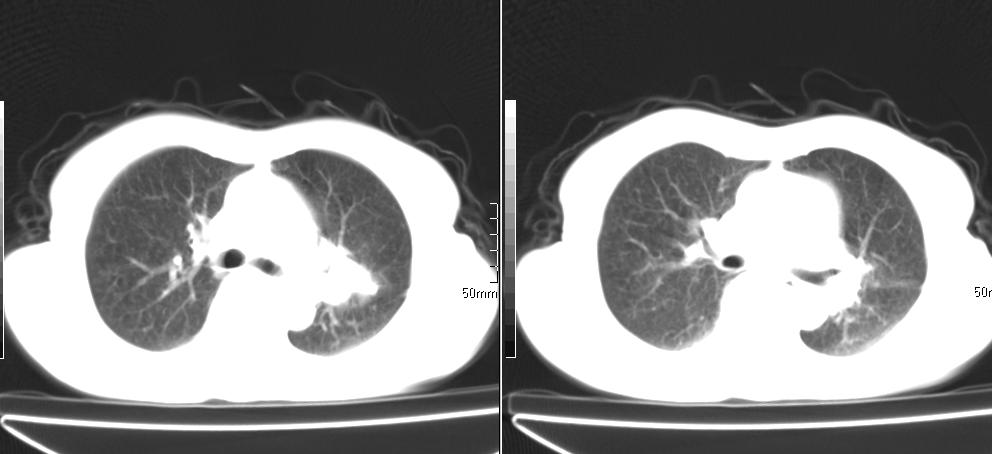

标题: CT26857:女,60岁,胃部不适前来就诊,不咳嗽,乏力,胸椎 [打印本页]

标题: CT26857:女,60岁,胃部不适前来就诊,不咳嗽,乏力,胸椎

1、胸椎有骨质破坏伴周软组织,考虑胸椎转移。2、考虑左肺上叶尖后段支气管开口区周围型肺癌可能。

1、胸椎有骨质破坏伴周软组织,考虑胸椎转移。2、考虑左肺中央型肺癌可能。

1)考虑左肺中央型肺癌。2)胸椎转移瘤不排除;建议行mri检查。

左肺中央型肺癌,胸椎大致正常,必要时ect扫描